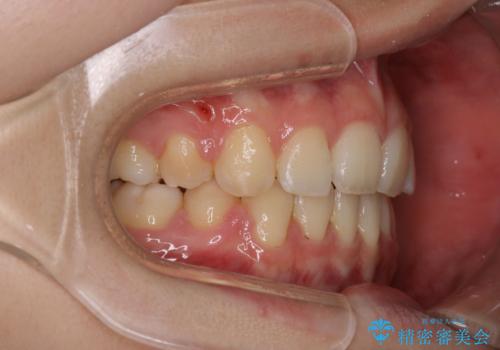

ワイヤーによる抜歯矯正でガタガタの改善

- 前歯のがたがたを主訴に来院されました。

上下の前歯が前方に傾斜しているのもあり、内側に前歯をひっこめるために上下左右の歯を1本ずつ抜歯して矯正することとしました。

ガタガタも改善しましたが、前歯が内側に引っ込むことにより口元もすっきりして、唇が閉じやすくなりました。